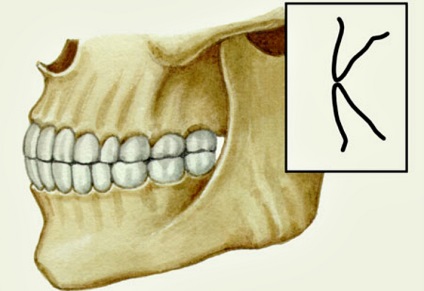

Mi az a szint harapás

Általában a felső szélén normál elzáródás fogazat egységek szélein túlnyúlhat az alsó metszőfogak. És az előre vágóélek a fogak harapni a felső és az alsó állkapocs egymáshoz érjenek.

Fontos! Tétreharapás - a patológia, amelyben a frontális kezelőegység állapotban „közös közös.” A normális körülmények között figyelembe, amikor fedi az alsó fogsor által hordozott harmadik bit hosszúságú. Tekintettel arra, hogy a közvetlen elzáródás figyelhető helytelen aránya fogai csak javított erasability fogszövettel. ×

Közvetlen elzáródás - olyan állapot, amikor a fogak a megfelelő helyzetben a rendellenességet, és harapás néhány esetben egyfajta elzáródás vezet a gyors kopás a fogak érintkezési pontok.

A képen egy tétre harapás fogak. Ez egyfajta élettani elzáródás, amelyben az alsó és felső fogak interlock vágóélek, a harapás olyan közel, hogy ideális.